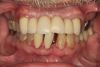

A 58-year-old male patient with existing maxillary and mandibular teeth presented with a concern that he may need extensive dental treatment. His clinical presentation included multiple crowns, a fixed partial denture, and numerous dental restorations. Additionally, he had concerns about his periodontal health after years of scaling and root planing procedures(Figure 2).Clinical examination revealed that while the patient presented with minimal caries and teeth fractures, he had generalized moderate to severe chronic periodontitis.

Fig 2. Patient presented with a failing dentition due to extensive periodontal disease and was interested in full-mouth reconstruction with dental implants.

Figure 2